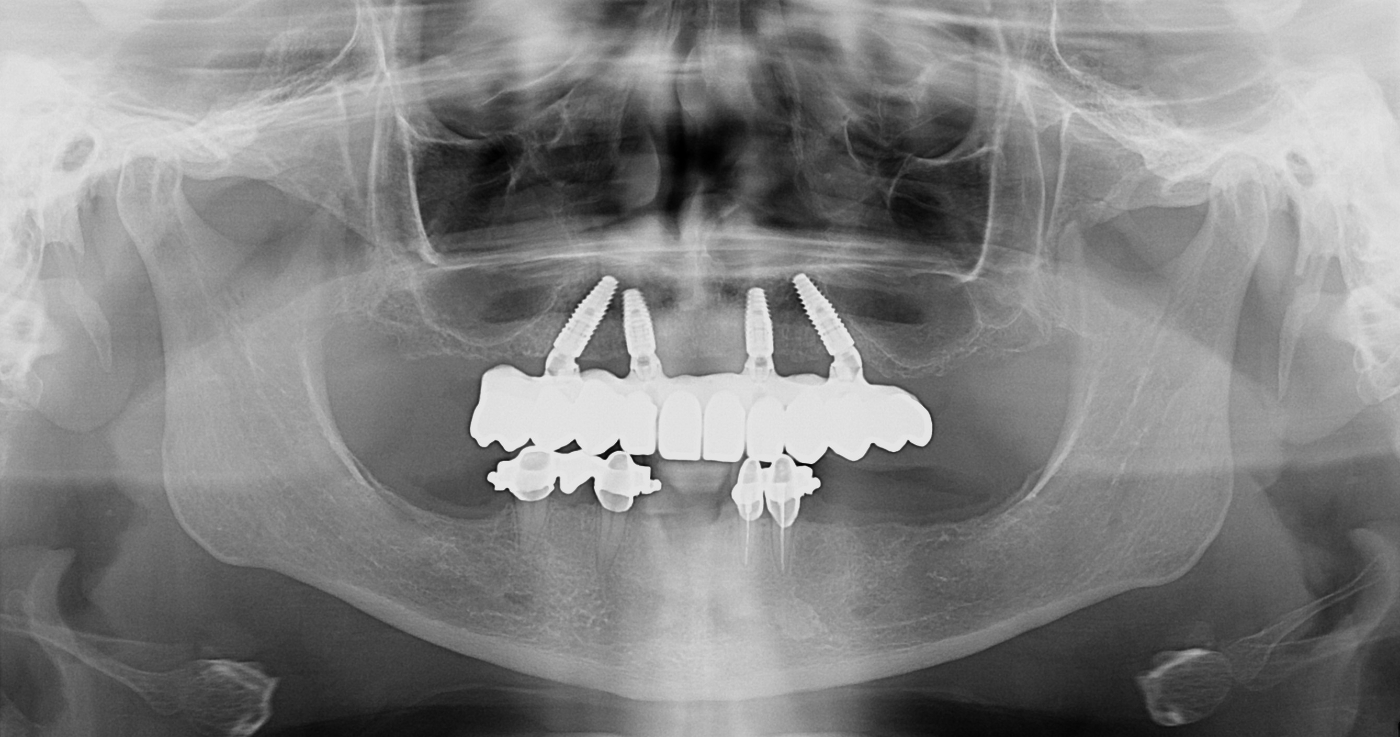

Ortopan snimka prije ugradnje All-on-4 implantata